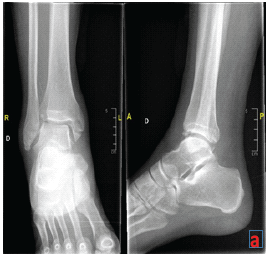

Chronic Syndesmotic Instability Associated with a Complex Lesion of the Posterior Inferior Tibiofibular Ligament: Review, Case Report, and Surgical Report

Virginie Perez , Nermine Habib , Angela Seidel

………………………………p.256-259